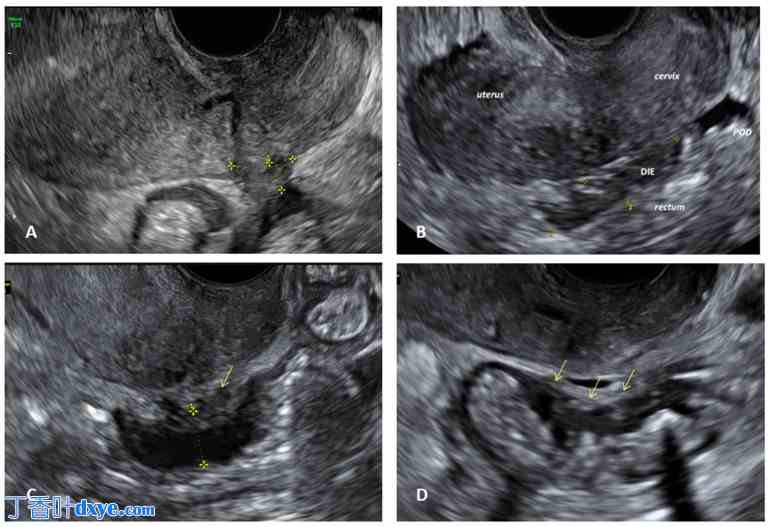

图 1.

卵巢子宫内膜异位症的经阴道超声 (TVS) 表现。(A) 子宫内膜异位症最典型的表现是单房囊性病变,囊壁光滑,呈“毛玻璃”状;(B) 双侧子宫内膜异位症(带星号)呈现“接吻卵巢”状。